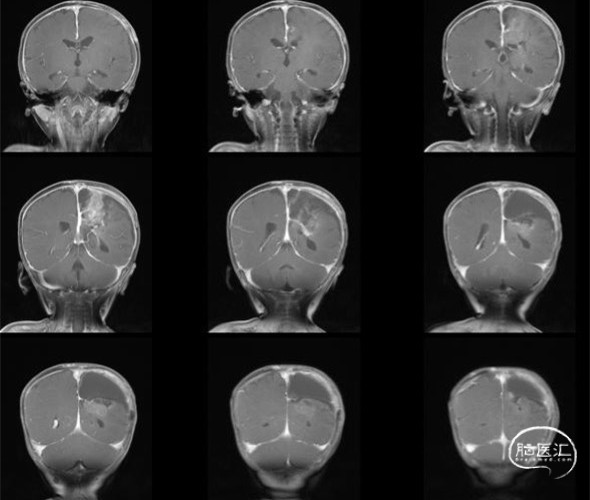

术后1月复查头部MRI